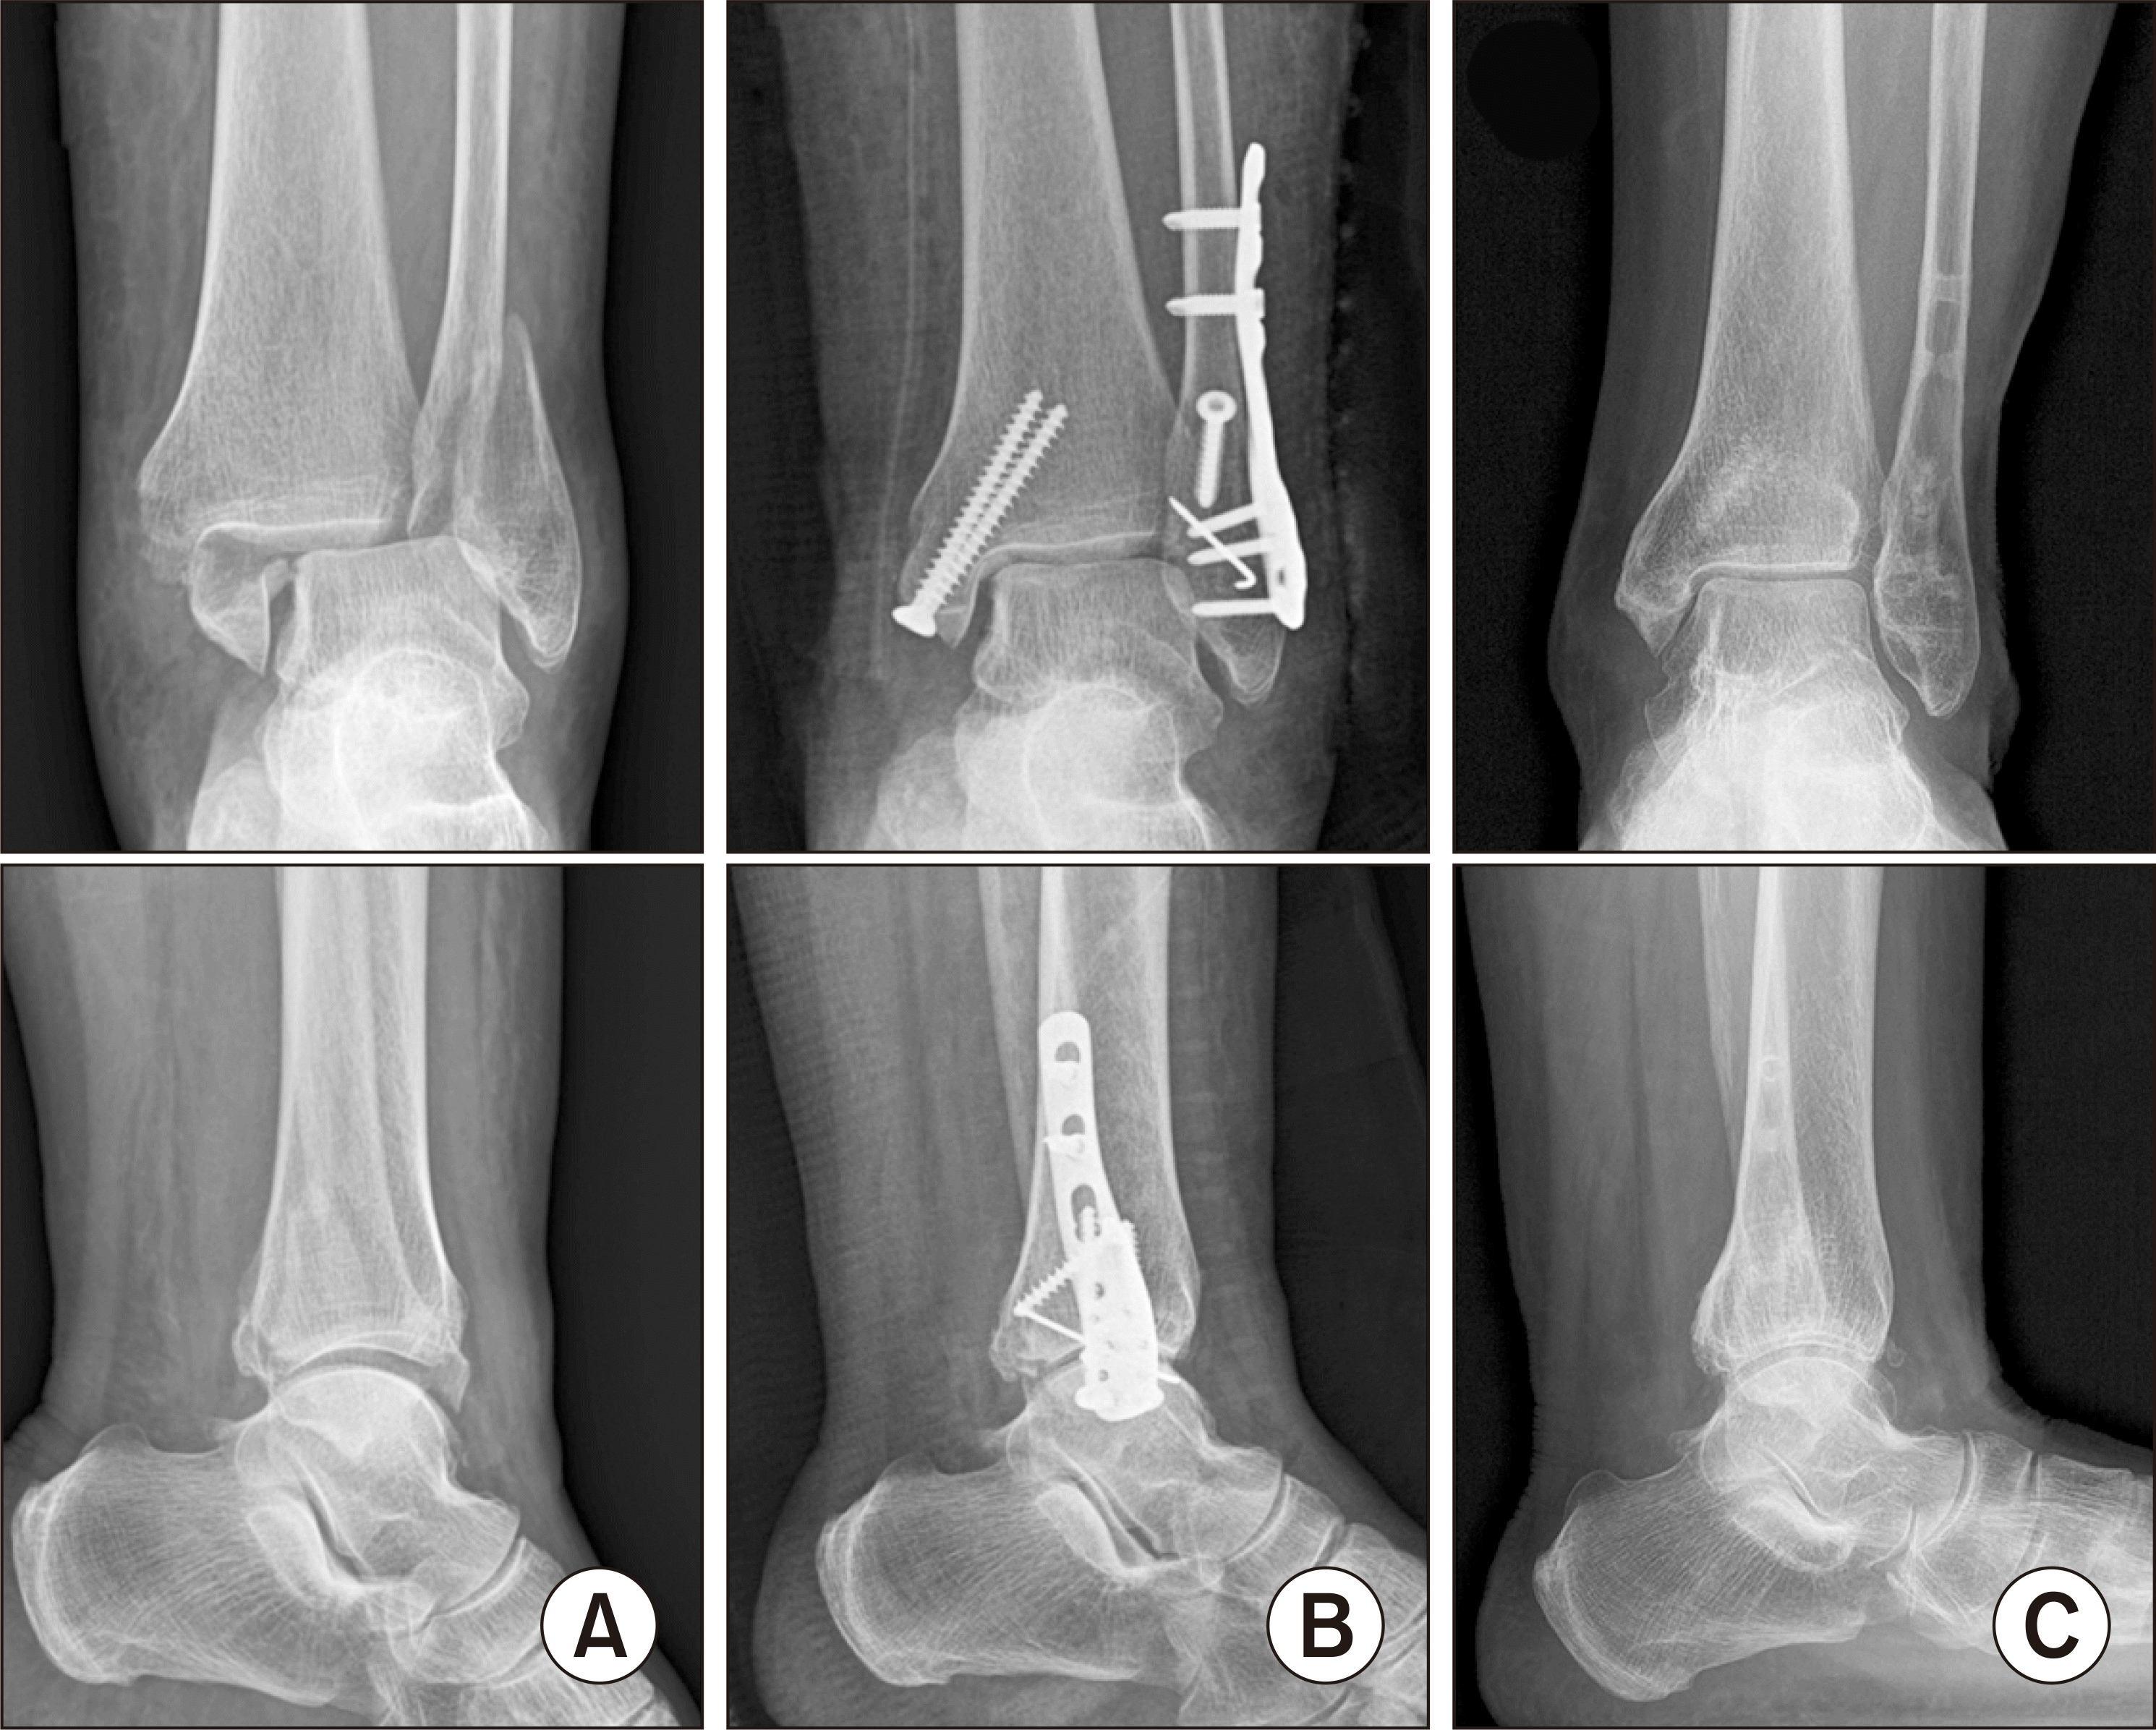

Figure 1

(A) Preoperative, (B) immediate postoperative, and (C) 1 year and 3 months postoperative radiographs of the 44-year-old male patient with bimalleolar fracture. A cortical screw was used in the lag screw technique for the lateral malleolar fixation.